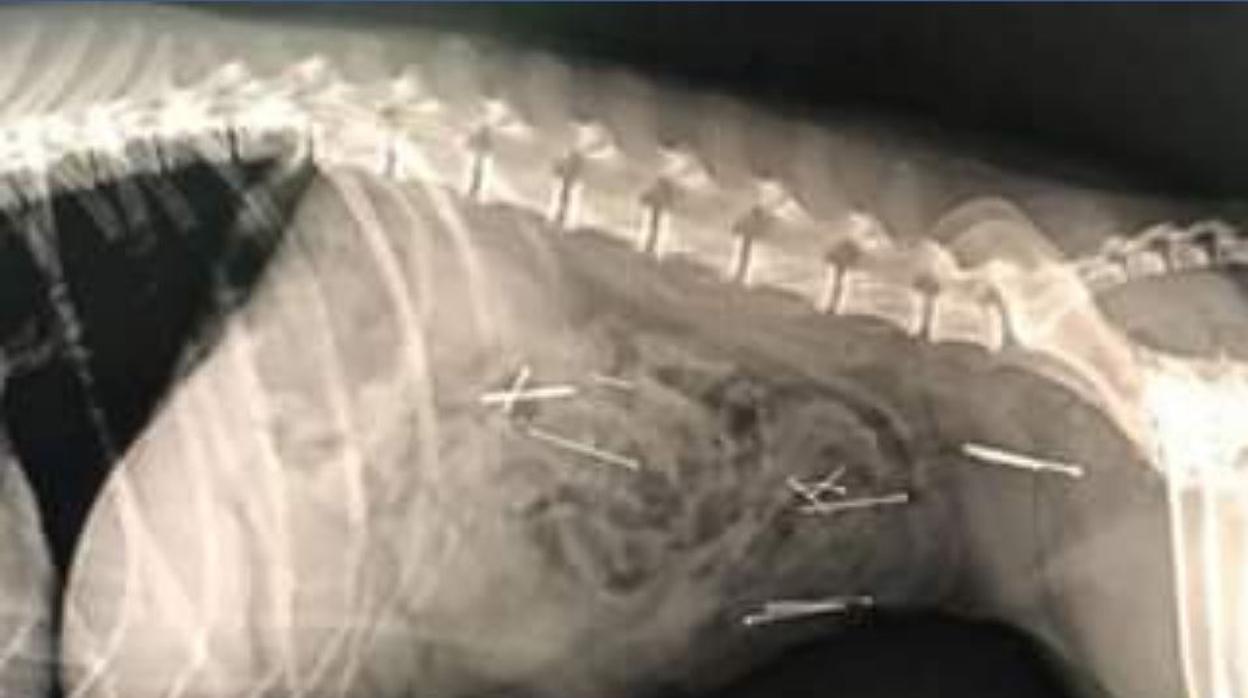

Radiografía realizada en el hospital veterinario Privet, en Brunete AYUNTAMIENTO DE BRUNETE

El Consistorio, que asegura haber recibido varios avisos al respecto, comparte la imagen de una radiografía, en la que se puede observar el estado del aparato digestivo de un perro que ha ingerido el cebo. Por culpa de esta actividad «inadmisible», dice el Ayuntamiento, varios alfileres descansan en el estómago del animal, que ahora está en «proceso de recuperación».